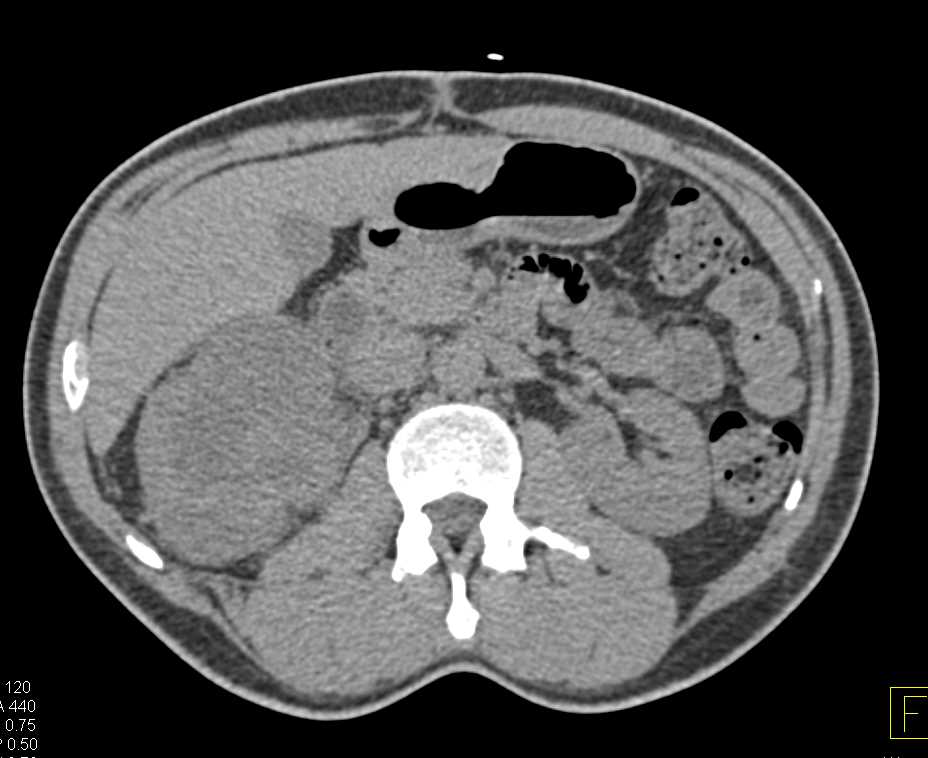

Renal Cell Carcinoma with Perirenal Spread in Right Kidney Using Cinematic Rendering